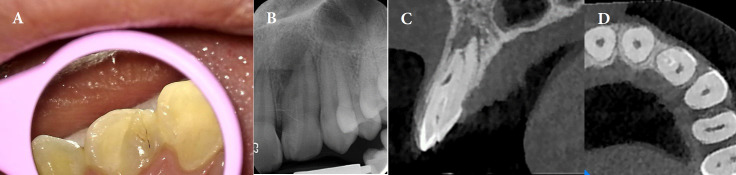

Dens invagination (DI) is a developmental dental anomaly characterized by the infolding of the enamel organ into the dental papilla. Type IIIb DI, involving deep invagination that extends apically along the root, poses significant challenges in endodontic treatment due to its complex anatomy. We describe a case of type IIIb DI in a 13-year-old female referred with the chief complaint of spontaneous pain on the left maxillary lateral incisor. Clinical examinations showed tenderness to percussion and palpation as well as a positive response to cold test with lingering pain. Cone-beam computed tomography (CBCT) confirmed the presence of type IIIb DI associated with a periapical lesion. The final diagnosis was irreversible pulpitis with apical periodontitis for main canal (distal) and pulpless and infected root canal system with secondary acute apical periodontitis according to Abbott classification for the other canal. Two separate access cavities were prepared with the guidance of CBCT. Root canal therapy was performed on both root canals, using photodynamic therapy (PDT) and ultrasonic-activated sodium hypochlorite for enhanced disinfection. Calcium-enriched mixture cement was used to obturate the apical third, followed by thermoplastic gutta-percha in the middle and coronal thirds. The patient was asymptomatic at 6- and 12-month follow-ups, with radiographic evidence of complete healing. This case highlights the effectiveness of conservative endodontic treatment using PTD in managing complex DI cases, with a focus on maintaining tooth structure and achieving long-term success.

Abstract Image